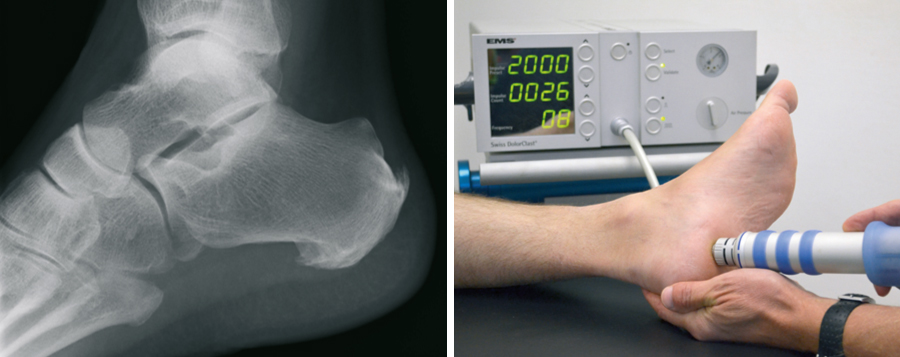

Fersensporn

Der plantare Fersensporn (unten an der Ferse) entsteht durch eine Überlastung der das Fußlängsgewölbe verspannenden Faszie. Bindegewebsschwäche, Fehlbelastung, Fehlstellung, aber auch Übergewicht können hierfür verantwortlich sein. Durch die Überlastung entsteht zwischen dem Fersenbein und der Anhaftungsstelle dieser Faszie eine zunehmende Gewebeschädigung, verbunden mit einer Verknöcherung, dem sogenannten Fersensporn. Nicht der Sporn selbst, sondern diese Gewebeschädigung verursacht die Schmerzen. Sie treten zunächst vorwiegend belastungsabhängig auf, später aber auch in Ruhe. An erster Stelle der möglichen Behandlungen steht die Versorgung mit speziellen orthopädischen Einlagen. Auch Injektionen, direkt an den Fersensporn, haben ihren Stellenwert. Sehr bewährt hat sich die risikofreie Stoßwellentherapie, die auch in unserer Praxis durchgeführt wird. Alternativ kann Röntgenbestrahlung eine Ausheilung bewirken.